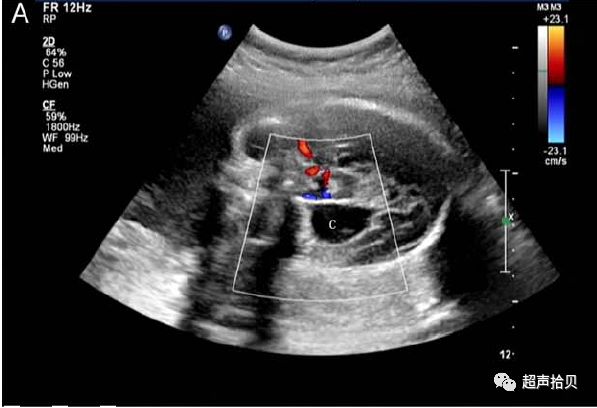

图4:图4A,25次妊娠时获得的横向声像图。 病变最初被诊断为蛛网膜

囊肿(C)伴有出血(H)。 B,妊娠26孕妇的产前MRI T2加权横向图像显示硬脑膜窦性畸形(D)合并血栓形成(T)